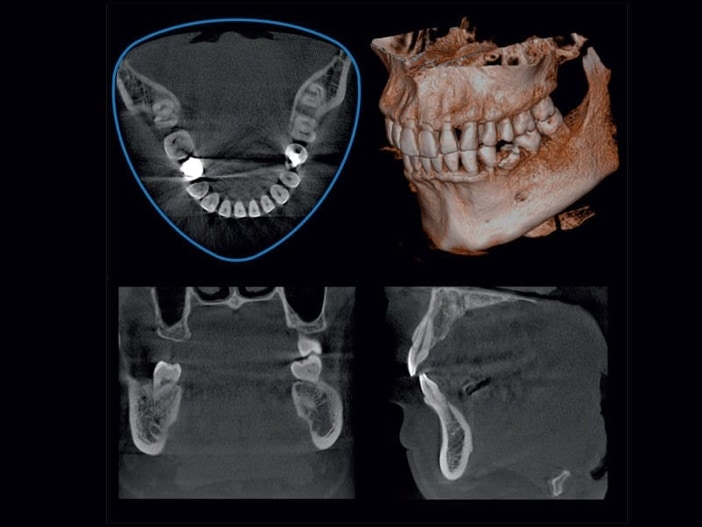

3D Röntgen mit digitaler Volumentomographie (DVT)

Durch unsere digitale 3D Röntgenanlage können wir die Strahlung, der Sie ausgesetzt sind, im Vergleich zum konventionellen Röntgen um bis zu 90 % verringern.

Unser modernes Röntgen- und Computersystem ermöglicht es uns, die aufgenommenen Röntgenbilder sofort am Monitor darzustellen und zu bearbeiten. Das hohe Auflösungsvermögen  gewährleistet eine genaue und sichere Diagnose und gibt uns und Ihnen die Möglichkeit, anhand der Darstellung am Monitor gemeinsam eine exakte Behandlungsplanung zu erarbeiten.

Was habe ich durch das DVT 3D Röntgen für Vorteile?

Die Digitale Volumentomographie (DVT) ist ein hochmodernes dreidimensionales Röntgenverfahren. Diese Methode ermöglicht dem Zahnarzt, die Strukturen (z.B. Knochen, Zähne, Nervverläufe) im Kieferbereich dreidimensional zu betrachten und dadurch die vorgesehene Behandlung präzise zu planen.

Das DVT 3D Röntgen ermöglicht eine präzise Diagnostik: Die hochauflösenden 3D-Bilder liefern ein sehr genaues Abbild der knöchernen Strukturen, der Zähne und Zahnwurzeln. Eingriffe, wie Implantationen, können exakt geplant werden und Nervverletzungen vermieden werden.

Auch bei unklaren Beschwerden kann das DVT helfen. Zähne und Zahnwurzeln können dreidimensional dargestellt und von allen Seiten "beleuchtet" werden. So können Prozesse sichtbar werden, die beim herkömmlichen Röntgen von anderen Strukturen verdeckt werden.